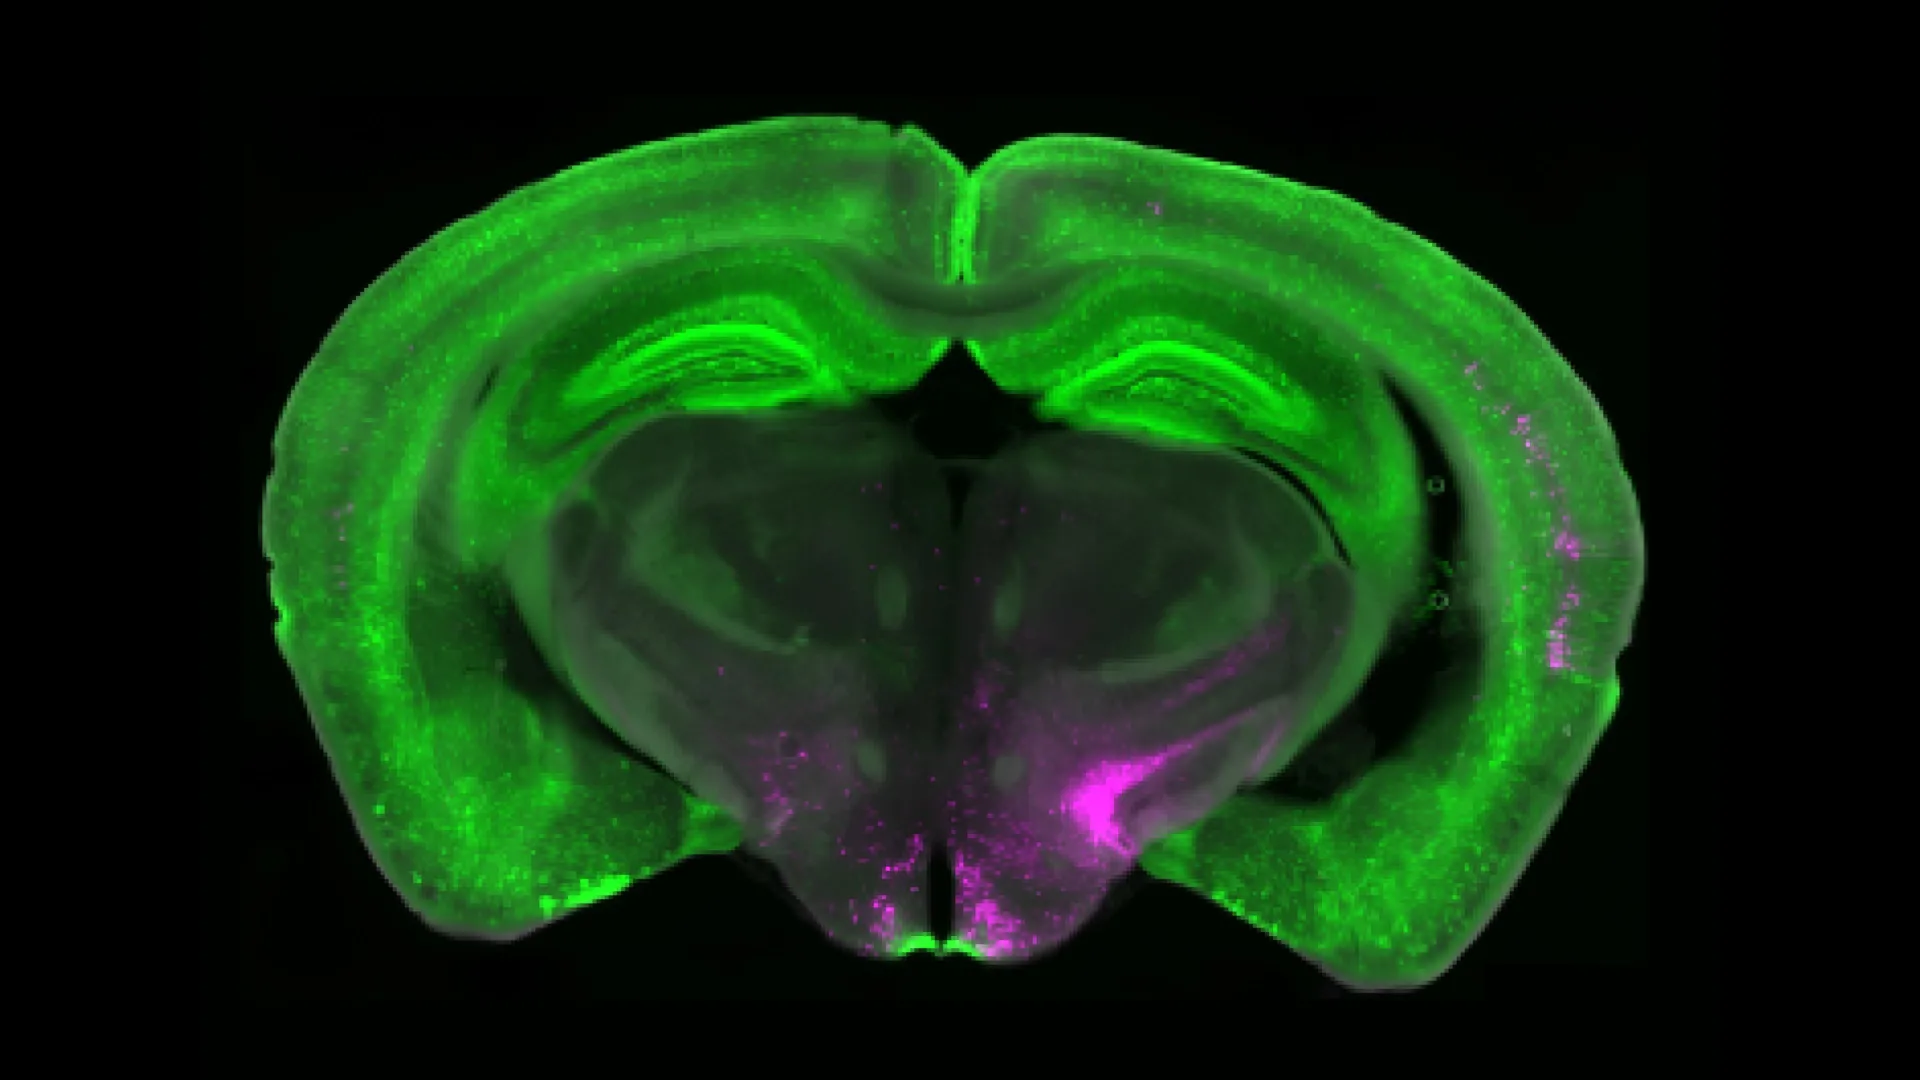

Betley descobriu uma parte importante do quebra-cabeça da dor crônica com associados da Universidade de Pittsburgh e do Scripps Research Institute. Sua pesquisa aponta para um grupo específico denominado receptor Y1 (Y 1R) que está localizado no núcleo parabraquial lateral (LPBN). Esses neurônios são ativados no reino da dor sem fim, mas também processam sinais relacionados à fome, ao medo e à sede. Sugere que o cérebro pode ajustar as reações à dor quando outras necessidades mais urgentes são necessárias.

Trabalhando com o Laboratório Taylor da Universidade de Pittsburgh, a equipe de Betlie usou imagens de cálcio para imaginar neurônios em tempo real em modelos de dor de curto e longo prazo. Eles observaram que Y1 e Neurônios não respondem apenas à rápida explosão de dor; Em vez disso, eles continuaram a disparar continuamente durante a dor prolongada, o que é conhecido como “atividade tônica”.

Os pesquisadores também identificaram a identidade molecular e fisiológica do Y1 e do Neurônio no LPBN. Eles descobriram que os neurônios Y1 não formavam duas populações fisiológicas ou moleculares. Em vez disso, esses neurônios foram espalhados por muitos outros tipos de células.

“É um carro estacionado para ver”, diz Betley. “Esperamos que todos os Wi 1 e Neurons se tornem um monte de carros amarelos estacionados juntos, mas aqui o Y1 e os Neurons são como carros amarelos, carros azuis e carros verdes. Não sabemos exatamente Por queMas achamos que essa distribuição em mosaico pode amortecer diferentes tipos de estímulos dolorosos em vários circuitos do cérebro”.